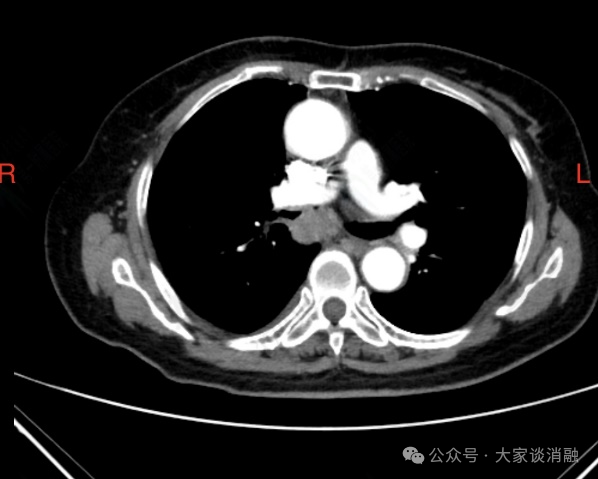

夏奶奶近两年来一直被间断的胸闷、气短、咳嗽、咳痰困扰。半月前,她的病情急剧加重,出现了痰中带血的症状,家人紧急送至东院区。呼吸与危重症医学科阎杰副主任医师接诊后,立即为夏奶奶进行胸部增强CT检查。结果提示“右肺门增大,右肺主支气管内结节状软组织密度灶,右肺下叶不张”,高度怀疑恶性肿瘤。

*患者CT检查